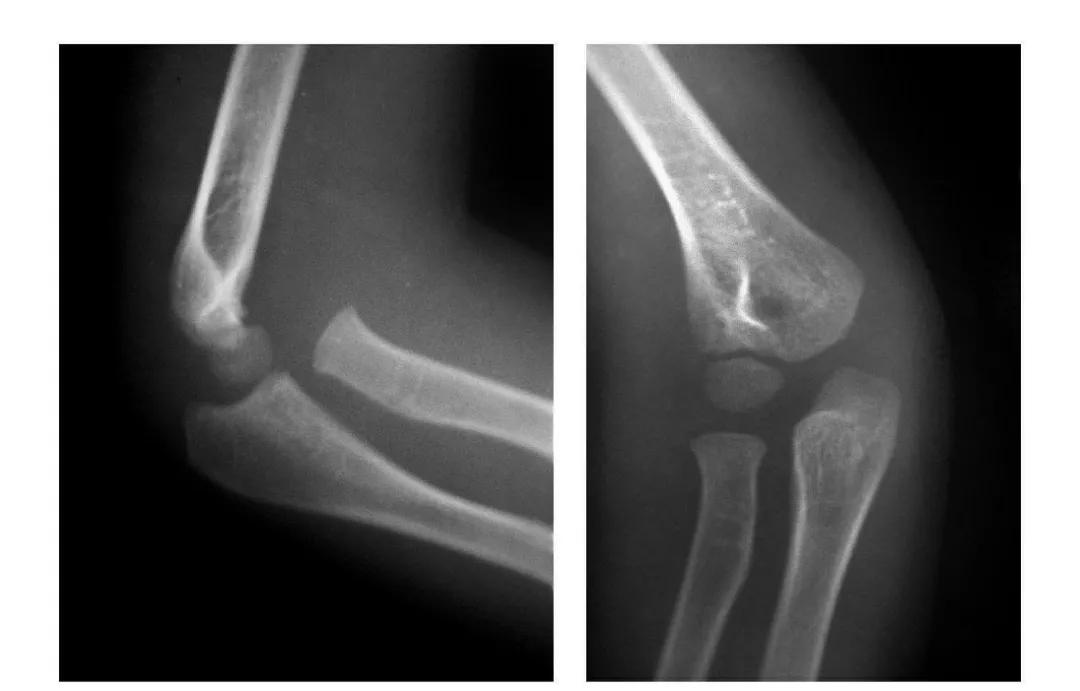

尺骨近端骨折

尺骨鹰嘴骨折

例1:儿童鹰嘴突无移位骨折。

例2:成人鹰嘴突骨折。

例3:尺骨鹰嘴根部骨折并肘关节前脱位。

例4:尺骨鹰嘴劈裂骨折并桡骨头骨骺向后滑脱。

例5:尺骨鹰嘴劈裂骨折并桡骨头骨骺滑脱致该骨块向后上翻转移位。

例6:尺骨鹰嘴劈裂骨折并肱骨内上髁撕脱骨折。